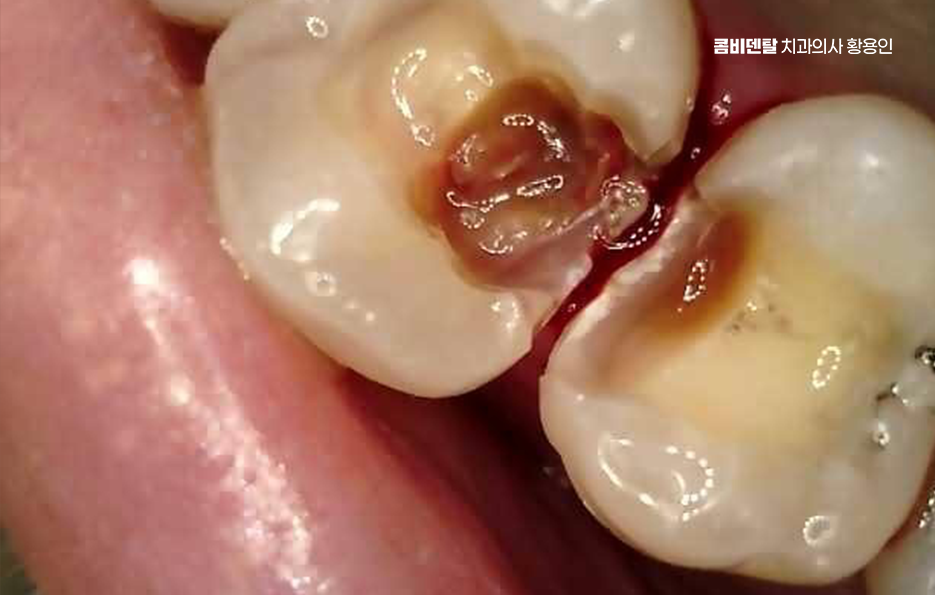

처음엔 안 보일 정도의 크랙이 생기고, 그 사이로 음식물과 세균이 침투하면서 2차 충치가 생기기 쉬운 것이며 특히 어금니처럼 씹는 힘이 센 부위에 들어간 아말감은 이런 팽창으로 인해 치아에 미세한 금을 만들고, 결국은 깨지거나 뿌리까지 손상이 가는 일이 생길 수 있기 때문에 늦지 않게 아말감 교체 레진 같은 재료로 재치료를 고려해야 할 수 있었어요

다음으로 아말감은 경계 부식이 문제가 될 수 있는데 접착력이 비교적 약한 편이라 시간이 지나면 테두리가 들뜨거나, 잇몸과의 접촉면에 틈이 생길 수 있고 이 틈은 결국 충치가 다시 생길 수 있는 통로가 될 수 있으며 아말감 아래쪽에 숨어서 진행되는 충치는 눈에 잘 띄지 않아서 발견이 늦어지는 경우가 많아서 나중에 발견되었을 땐 이미 신경까지 번져 있는 경우도 많이 있었어요

이런 아말감 부작용들이 의심되는 경우에는 조기에 제거하고 재치료 계획을 세우는 게 좋은데 재치료 방법은 크게 세 가지로 나뉘며 레진, 인레이, 크라운 순으로 치아의 손상 정도와 위치, 그리고 미용적인 요소를 종합해서 결정하는 거예요.